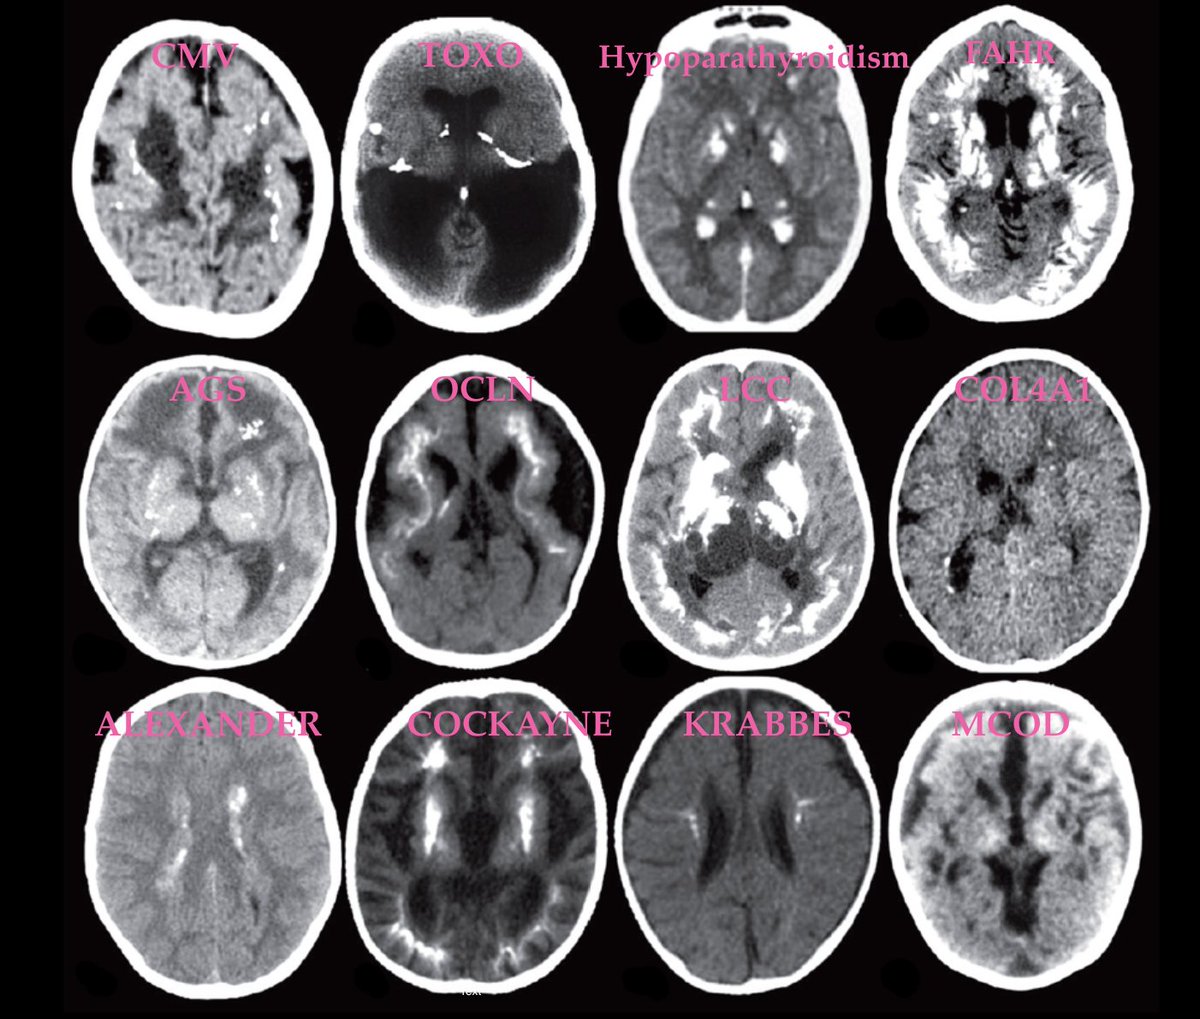

Intracranial calcifications in children, supplementary to AJNRcow submitted by Dr. Rahul Lakshmanan

@shmayyn https://onlinelibrary.wiley.com/doi/full/10.1111/dmcn.12359 … https://onlinelibrary.wiley.com/doi/epdf/10.1111/j.1469-8749.2012.04437.x …#Pedineurorad#neurorad#radres#radiology https://twitter.com/TheAJNR/status/1212846238644756480 …pic.twitter.com/gnToHOpgn8

Hvala. Twitter će to iskoristiti za poboljšanje vaše vremenske crte. PoništiPoništi -